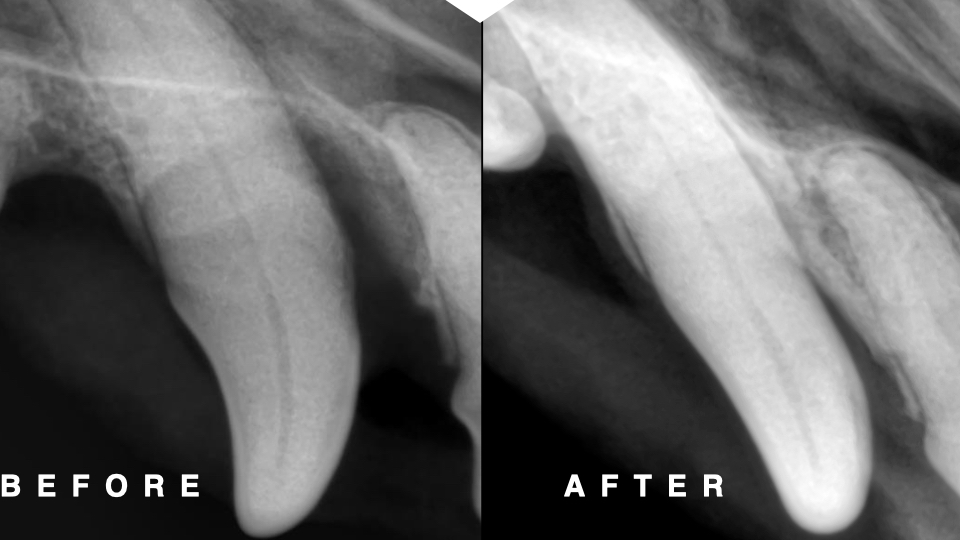

下の写真は処置時の歯槽骨と術後5ヶ月の歯科レントゲン写真です。

術後5ヶ月の歯科レントゲン撮影は無麻酔で行ったため、少し斜めになっていますが、歯槽骨が再生している所見が認められます。

歯周ポケットの深さも9mmから4mmに改善し、診断は重度歯周病(AL54%)から軽度歯周病(AL18%)まで改善しました。